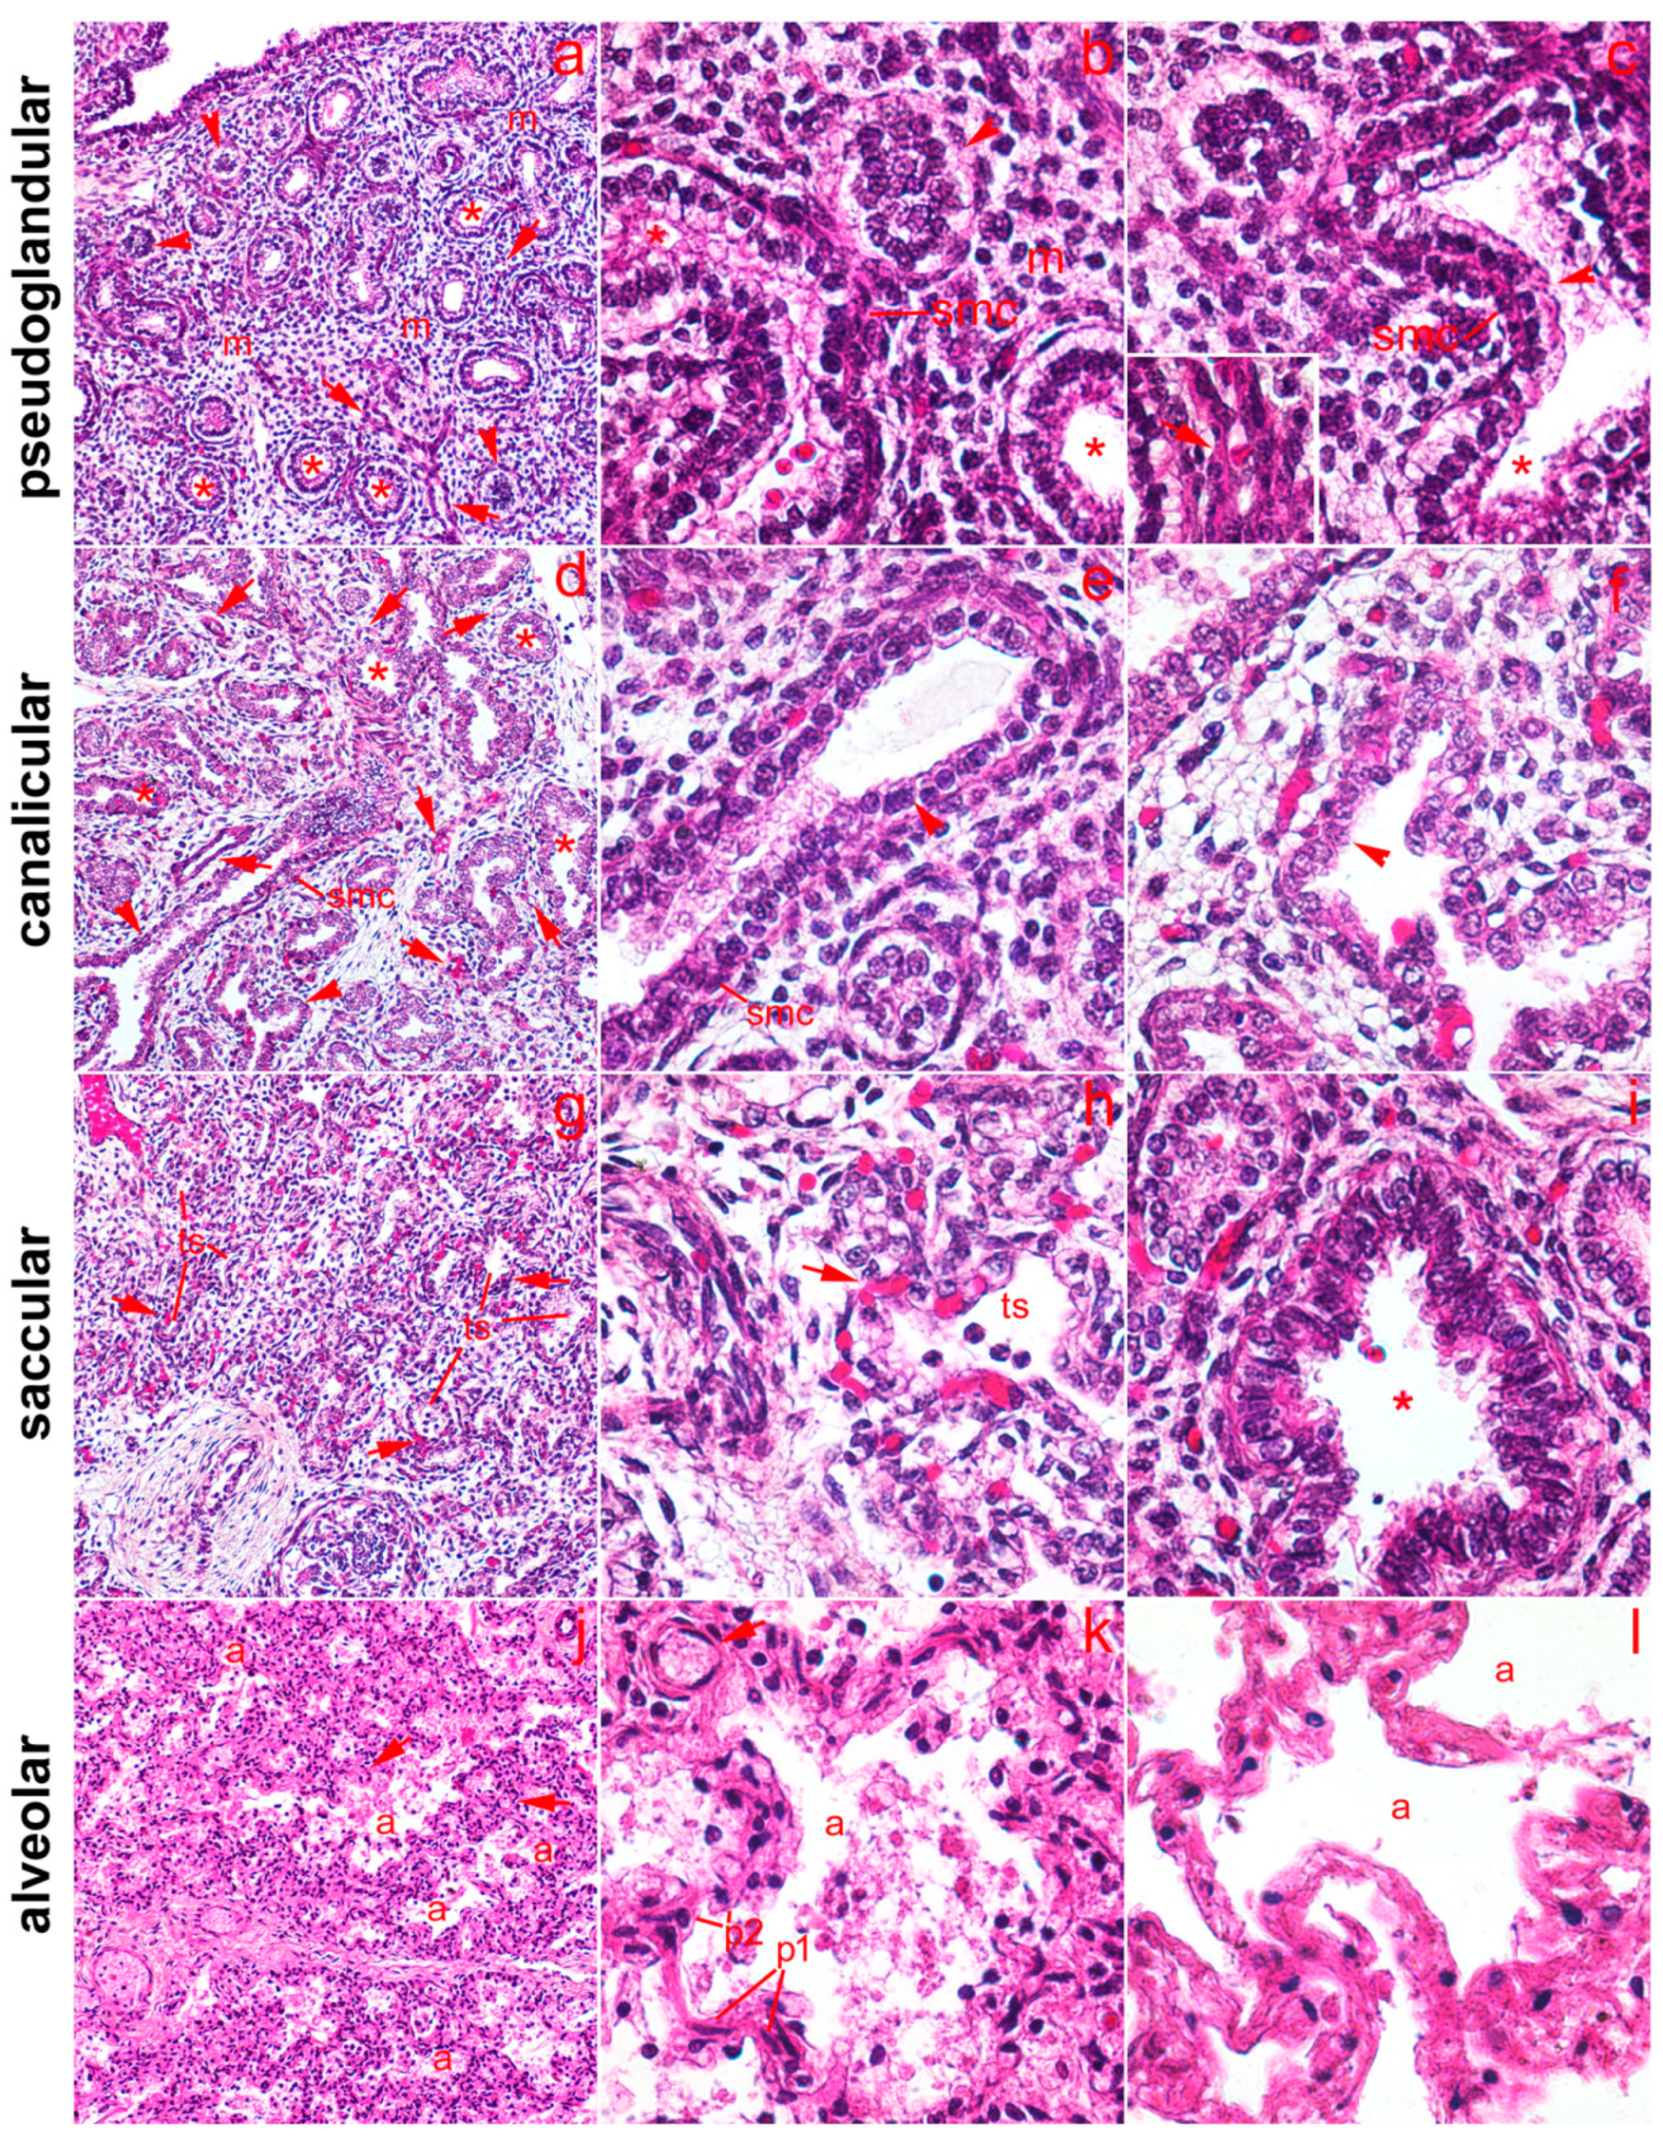

2.1. General Remarks

2.2. 5-HT1A Expression

2.3. 5-HT2A Expression

2.4. 5-HT3A Expression

2.5. Expression of Serotonin Receptors in Pneumocytes